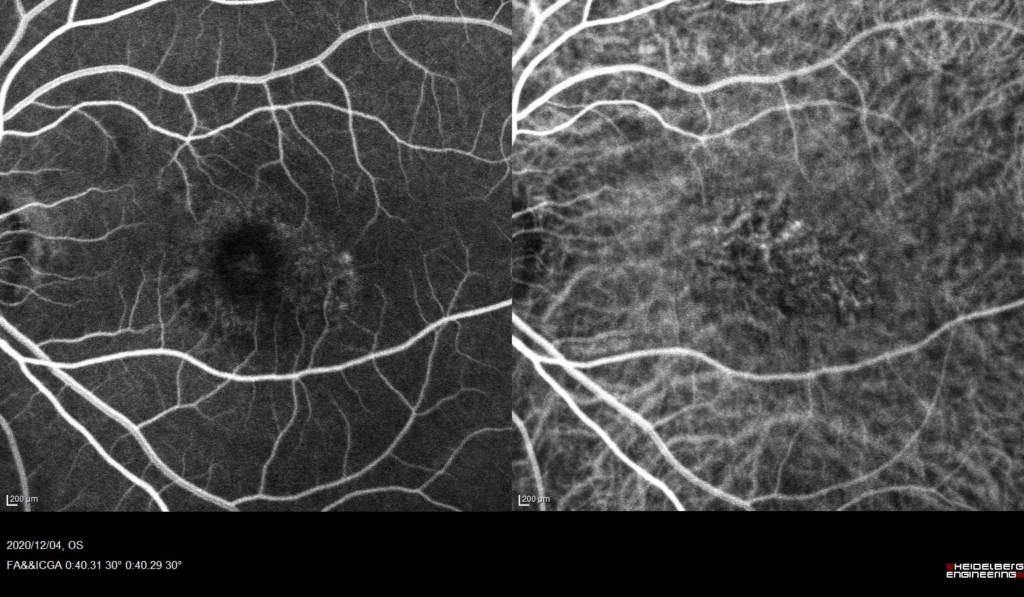

黄斑に、IAでCNVの網目状の血管がみられる。

FAでびまん性に漏出がみられる。